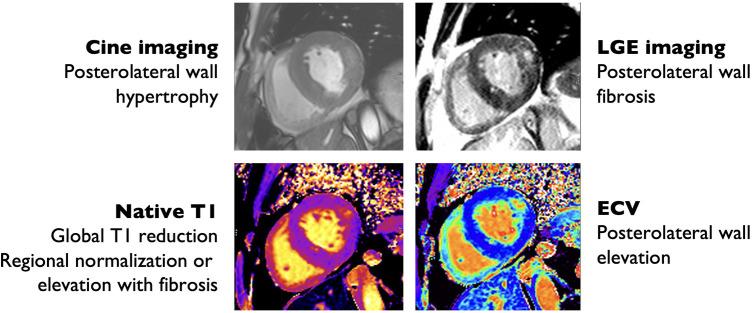

Anderson-Fabry disease (AFD) is an X-linked lysosomal storage disorder caused by deficient activity of the enzyme alpha-galactosidase. While AFD is recognized as a progressive multi-system disorder, infiltrative cardiomyopathy causing a number of cardiovascular manifestations is recognized as an important complication of this disease. AFD affects both men and women, although the clinical presentation typically varies by sex, with men presenting at a younger age with more neurologic and renal phenotype and women developing a later onset variant with more cardiovascular manifestations. AFD is an important cause of increased myocardial wall thickness, and advances in imaging, in particular cardiac magnetic resonance imaging and T1 mapping techniques, have improved the ability to identify this disease non-invasively. Diagnosis is confirmed by the presence of low alpha-galactosidase activity and identification of a mutation in the GLA gene. Enzyme replacement therapy remains the mainstay of disease modifying therapy, with two formulations currently approved. In addition, newer treatments such as oral chaperone therapy are now available for select patients, with a number of other investigational therapies in development. The availability of these therapies has significantly improved outcomes for AFD patients. Improved survival and the availability of multiple agents has presented new clinical dilemmas regarding disease monitoring and surveillance using clinical, imaging and laboratory biomarkers, in addition to improved approaches to managing cardiovascular risk factors and AFD complications. This review will provide an update on clinical recognition and diagnostic approaches including differentiation from other causes of increased ventricular wall thickness, in addition to modern strategies for management and follow-up.